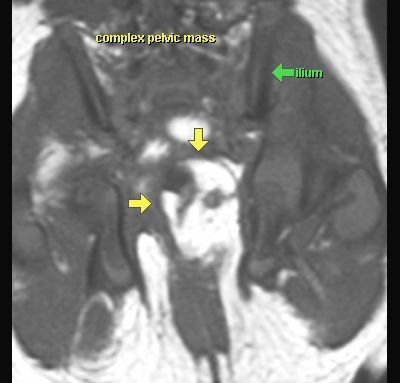

POTWORNIAK

MR